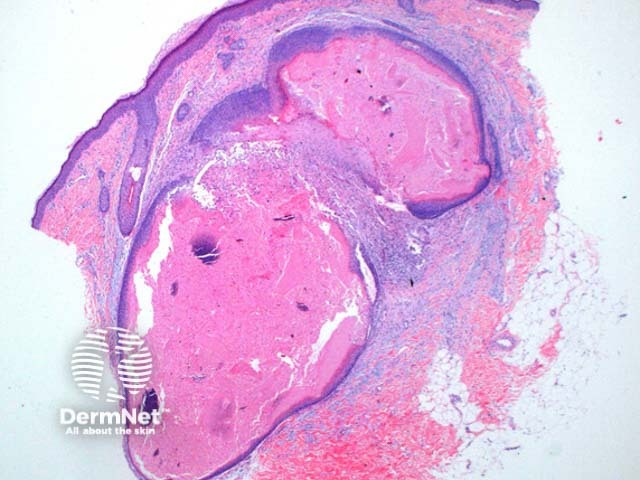

At low power the histological pattern seen in pilomatricoma is of a well-circumscribed nodulocystic tumour (Figure 2). While predominantly seen within the lower dermis, extension into the subcutaneous tissue is not uncommon. The tumour is comprised of a basaloid proliferation resembling the hair matrix cells, which matures into structureless eosinophilic cells lacking nuclei called shadow cells (Figures 3 and 4). The shadow cell area represents differentiation towards the hair cortex. Frequently there are areas of calcification within the shadow cell regions (Figure 5). A histiocytic infiltrate with multinucleated cells forms at sites of rupture (Figure 6).

Figure 2